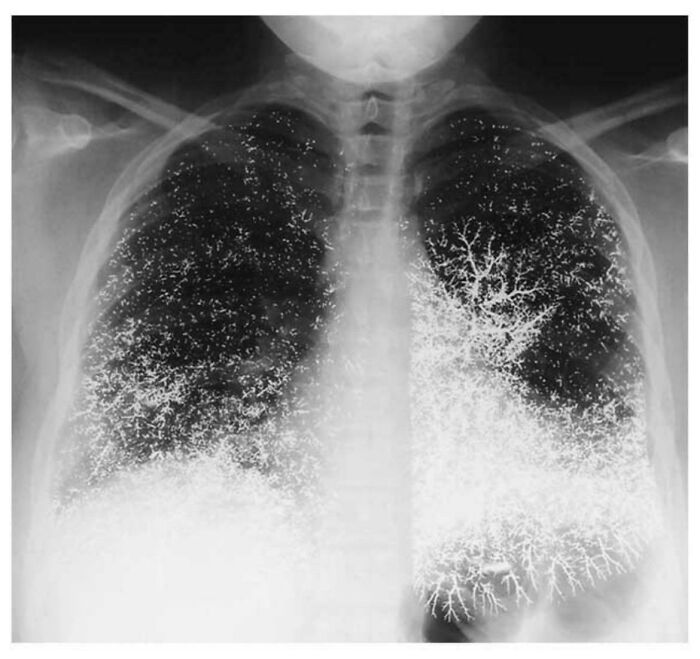

21-Year-Old Dental Assistant’s Chest X-Ray After a Crazy Mercury Incident